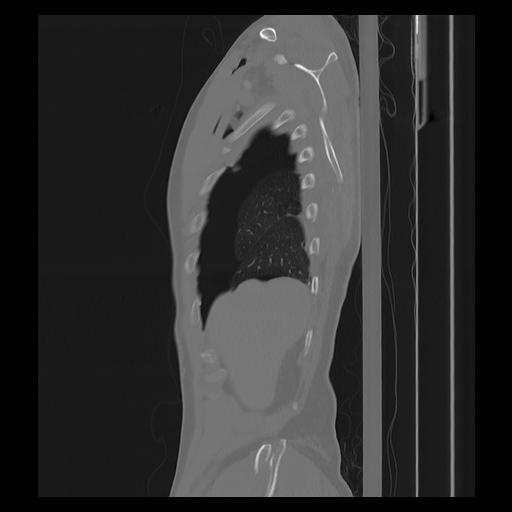

33 PULMON,CE,Sagittal,3.000,PULMON,Sagittal,